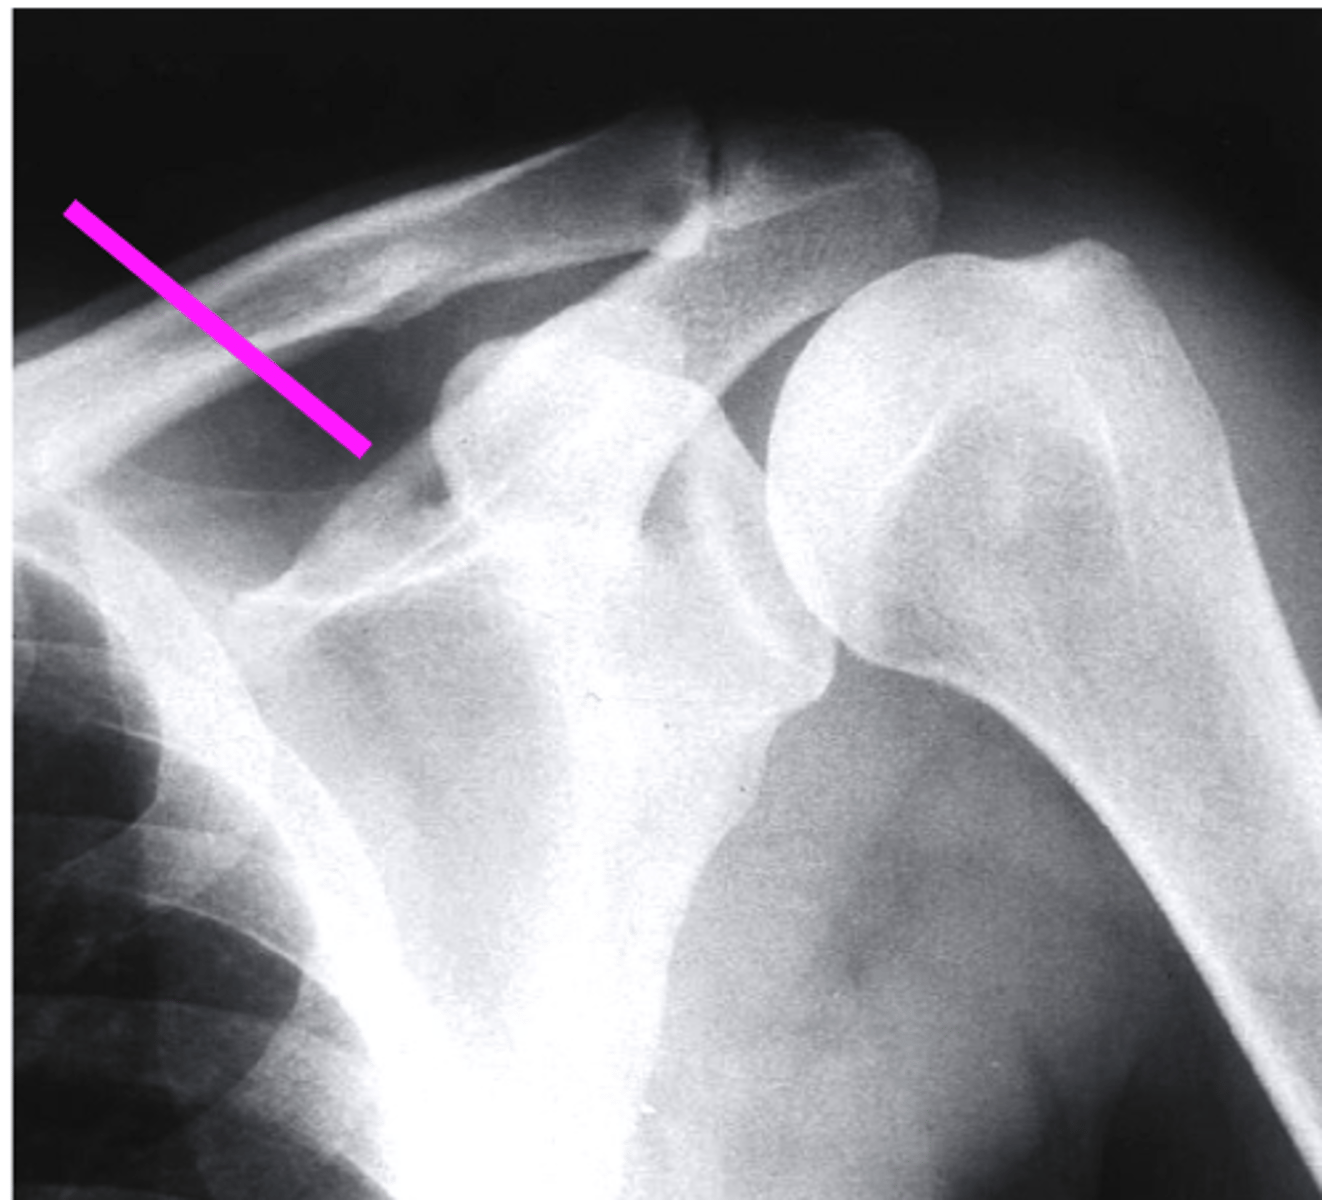

clavicle

what does the pink line point to?

spine of scapula

coracoid process

AC joint

acromion

Humeral Head

Greater Tuberosity

lesser tuberosity

Anatomic Neck of Humerus

Surgical Neck of Humerus

Shaft of Humerus

glenoid fossa

body of scapula

axillary border of scapula

vertebral border of the scapula